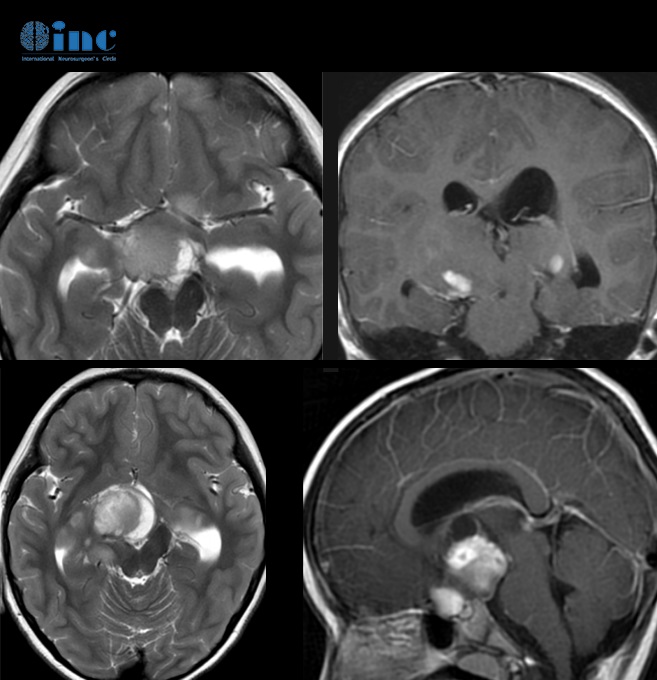

4、CT掃描:可為單側(cè)發(fā)病,也可為雙側(cè)發(fā)病,后者常伴發(fā)神經(jīng)纖維瘤病,并且兩側(cè)發(fā)病順序可不一致,應(yīng)引起重視。視神經(jīng)增粗扭曲為視神經(jīng)膠質(zhì)瘤較常見的表現(xiàn)。由于腫瘤壓迫,常使其前端的正常蛛網(wǎng)膜下腔擴(kuò)大。視神經(jīng)膠質(zhì)瘤眶內(nèi)部分為視神經(jīng)梭形或橢圓性腫大,也可呈管狀增粗,邊界清楚,密度均勻,腫瘤內(nèi)常見低密度的囊變區(qū)。約3%的腫瘤內(nèi)可見鈣化。

5、MRI檢查:表現(xiàn)為視神經(jīng)呈梭形、冠狀或橢圓形增粗,多數(shù)為中心性,少數(shù)為偏心形。與正常眼外肌比較,視神經(jīng)膠質(zhì)瘤在T1WI呈低信號(hào),T2WI呈高信號(hào),增強(qiáng)后中度強(qiáng)化。部分腫瘤壓迫使其前部正常的蛛網(wǎng)膜下腔擴(kuò)大,表現(xiàn)為與腦脊液信號(hào)相似的長T1、長T2信號(hào);由于少數(shù)腫瘤周圍蛛網(wǎng)膜等結(jié)構(gòu)反應(yīng)性增生而形成假性包膜,表現(xiàn)為長T1、長T2 。